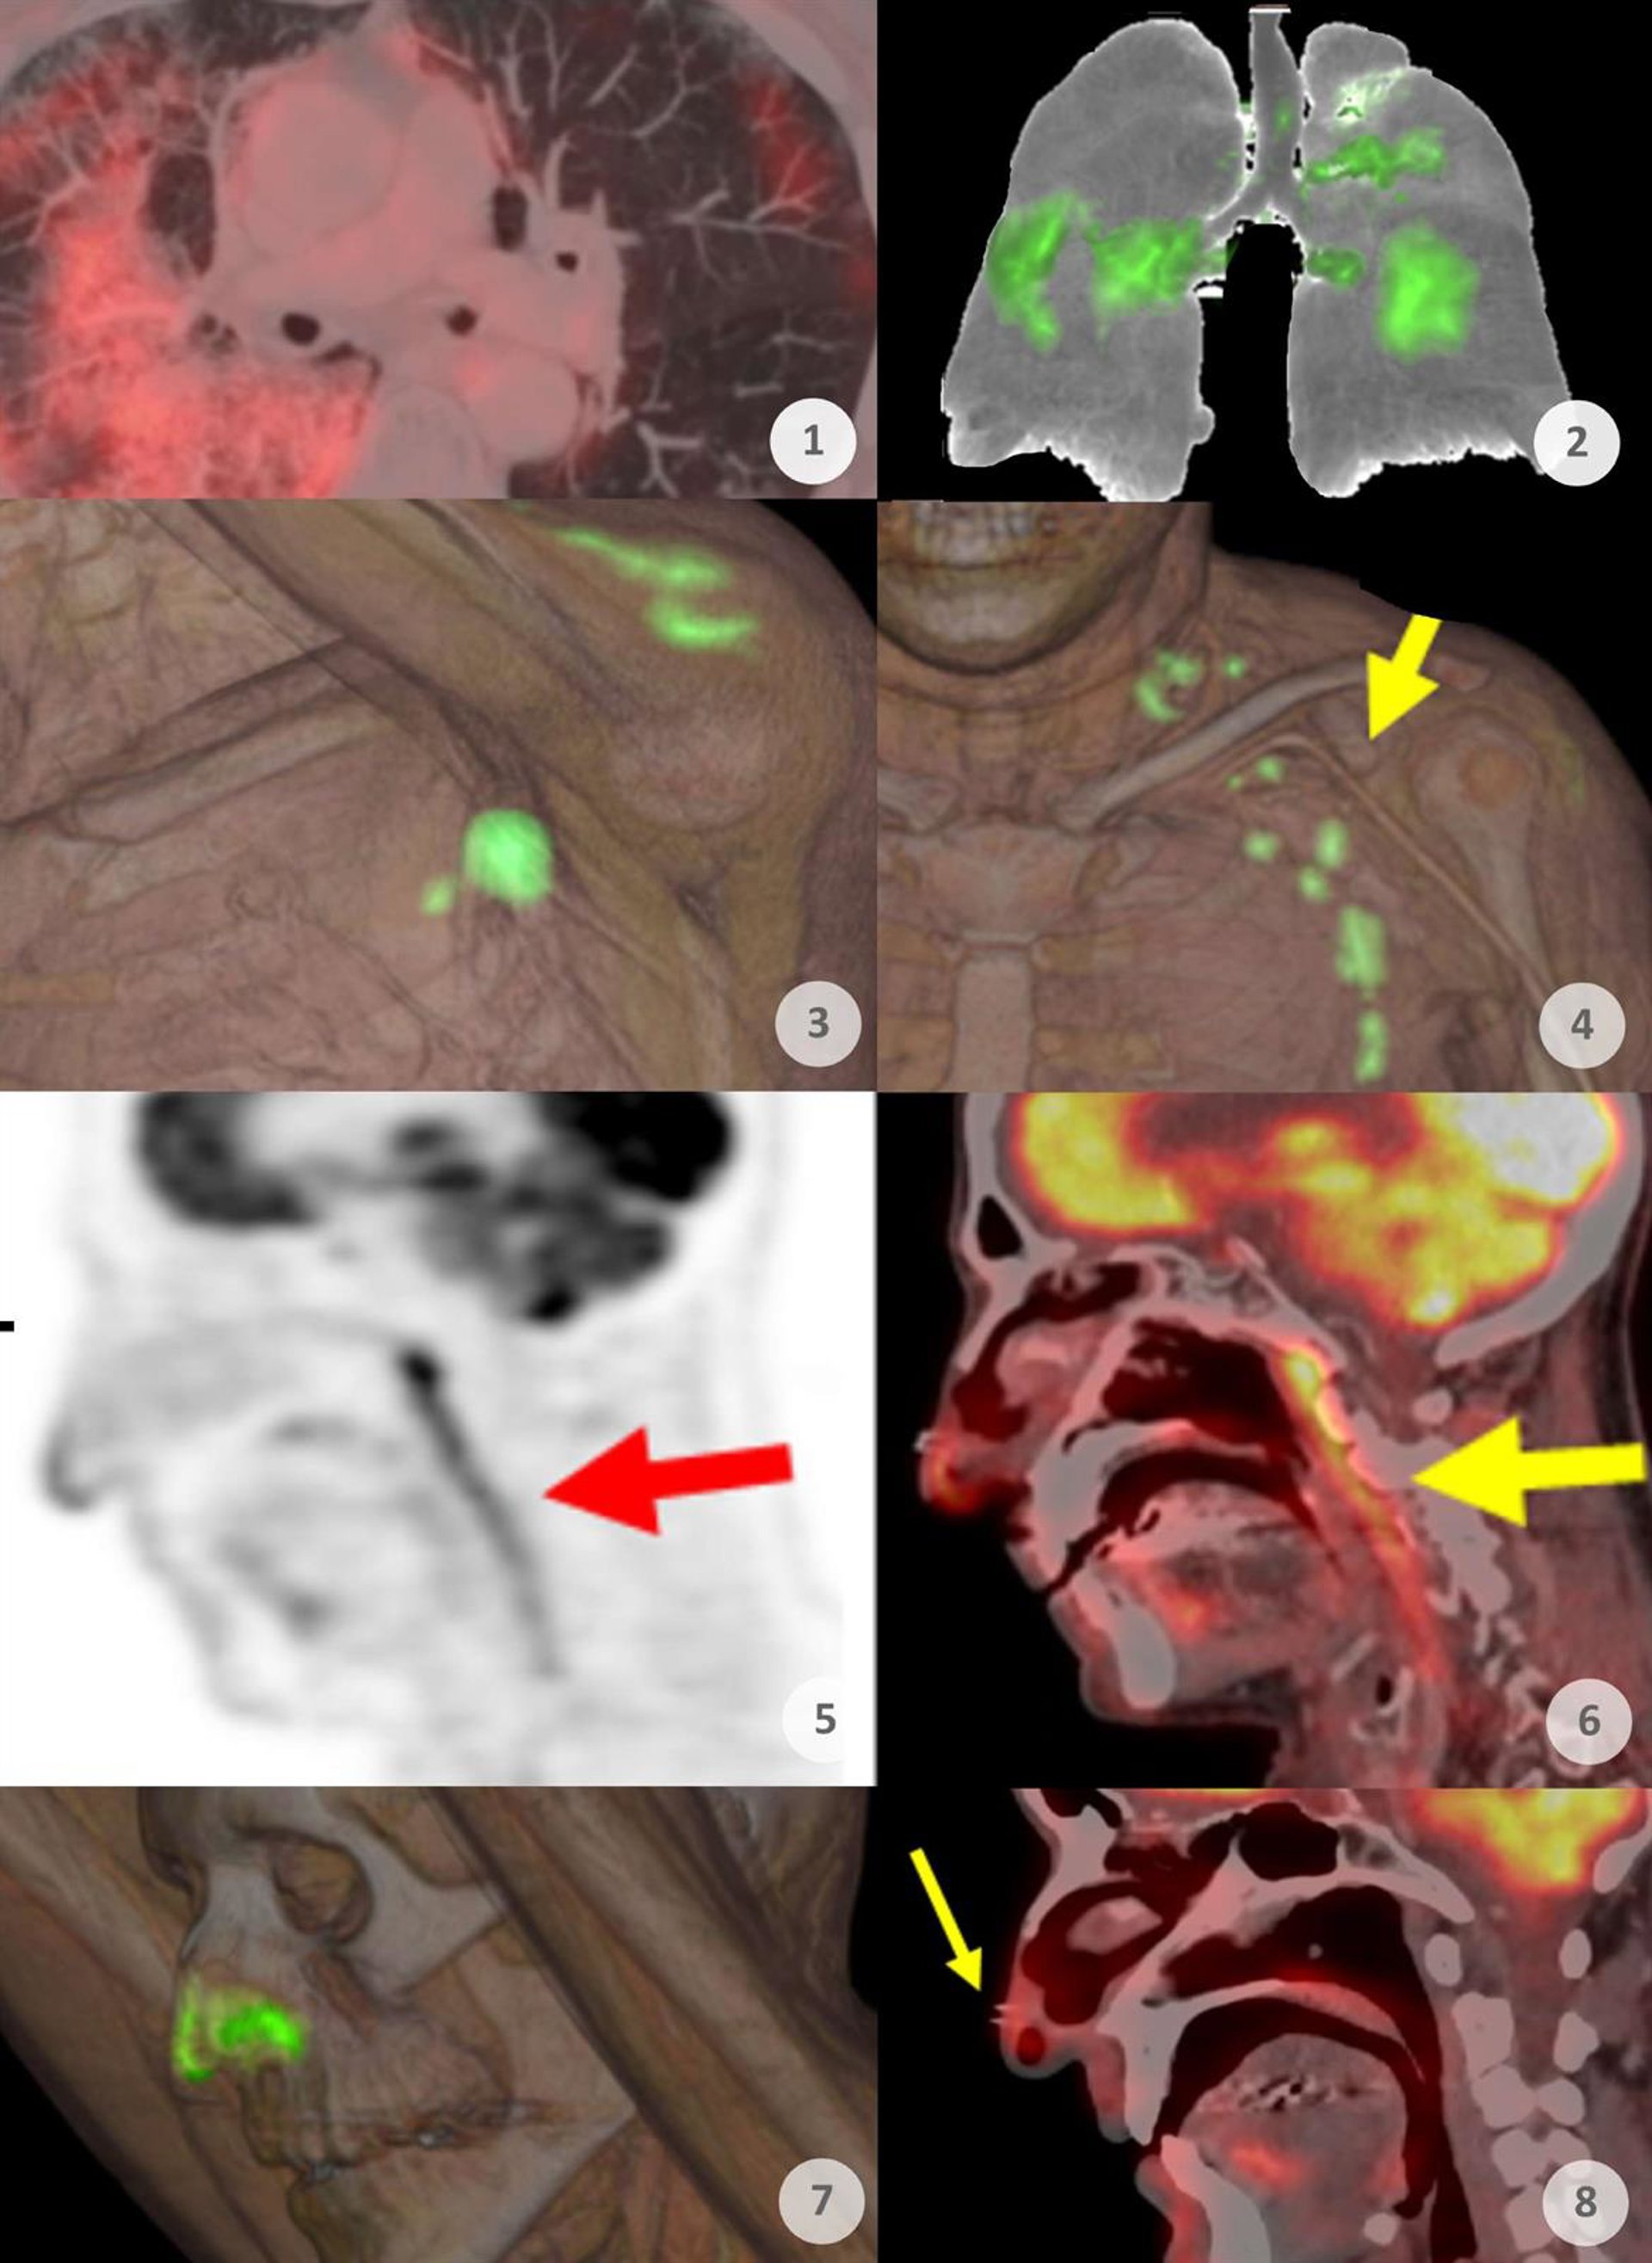

El Servicio de Medicina Nuclear del Hospital Universitario Quirónsalud Madrid, que desde el principio de la pandemia ha estado tratando a sus pacientes sometiéndoles a pruebas de PET-CT, muestra con sus imágenes cómo ha sido la evolución de la pandemia durante estos dos últimos años.

"Durante la primera ola, a partir de marzo de 2020, era muy frecuente observar afectaciones pulmonares. Llegó a apreciarse en el 4 por ciento de todos los pacientes a los que sometemos a pruebas PET", explica el doctor Antonio Maldonado, jefe del Servicio de Medicina Nuclear de Quirónsalud Madrid, que afirma que el COVID-19 no deja de ser una vasculitis sistémica que afectaba a vasos de diferentes niveles.

"Después, con el inicio de la vacunación desde principios de 2021, comenzamos a observar captaciones locales en la zona del hombro con extensión ganglionar, e incluso en el bazo debido a la vacunación. Observamos que en nuestra serie de pacientes la vacuna de Moderna fue la que más reacción producía, que generalmente provocaba también captación en los ganglios adyacentes a la zona de vacunación", añade.

En cambio, con la llegada y generalización de la variante ómicron a finales de 2021 se ha observado un cambio de patrón. "Ya no observamos afectaciones pulmonares como en la primera ola, sino que se aprecian con frecuencia captaciones en las mucosas oro y nasofaríngeas. Este nuevo patrón lo observamos desde diciembre de 2021", afirma.

Aparte del interés de observar cómo el PET-TC ha ido mostrando la evolución de la epidemia de la COVID-19, la difusión de estos hallazgos es importante para "que los médicos nucleares conozcan qué se están produciendo y valoren adecuadamente la presencia de estas captaciones en las imágenes para no alarmar innecesariamente al oncólogo, al paciente y para evitar procedimientos invasivos al paciente que no son necesarios. Es importante manifestar claramente en los informes que estos hallazgos son benignos para que no alteren el tratamiento de estos pacientes", analiza el doctor Maldonado que cree que la imagen PET ha puesto de manifiesto cómo iba evolucionando la pandemia, dando información de lo que estaba sucediendo dentro del cuerpo de los enfermos.